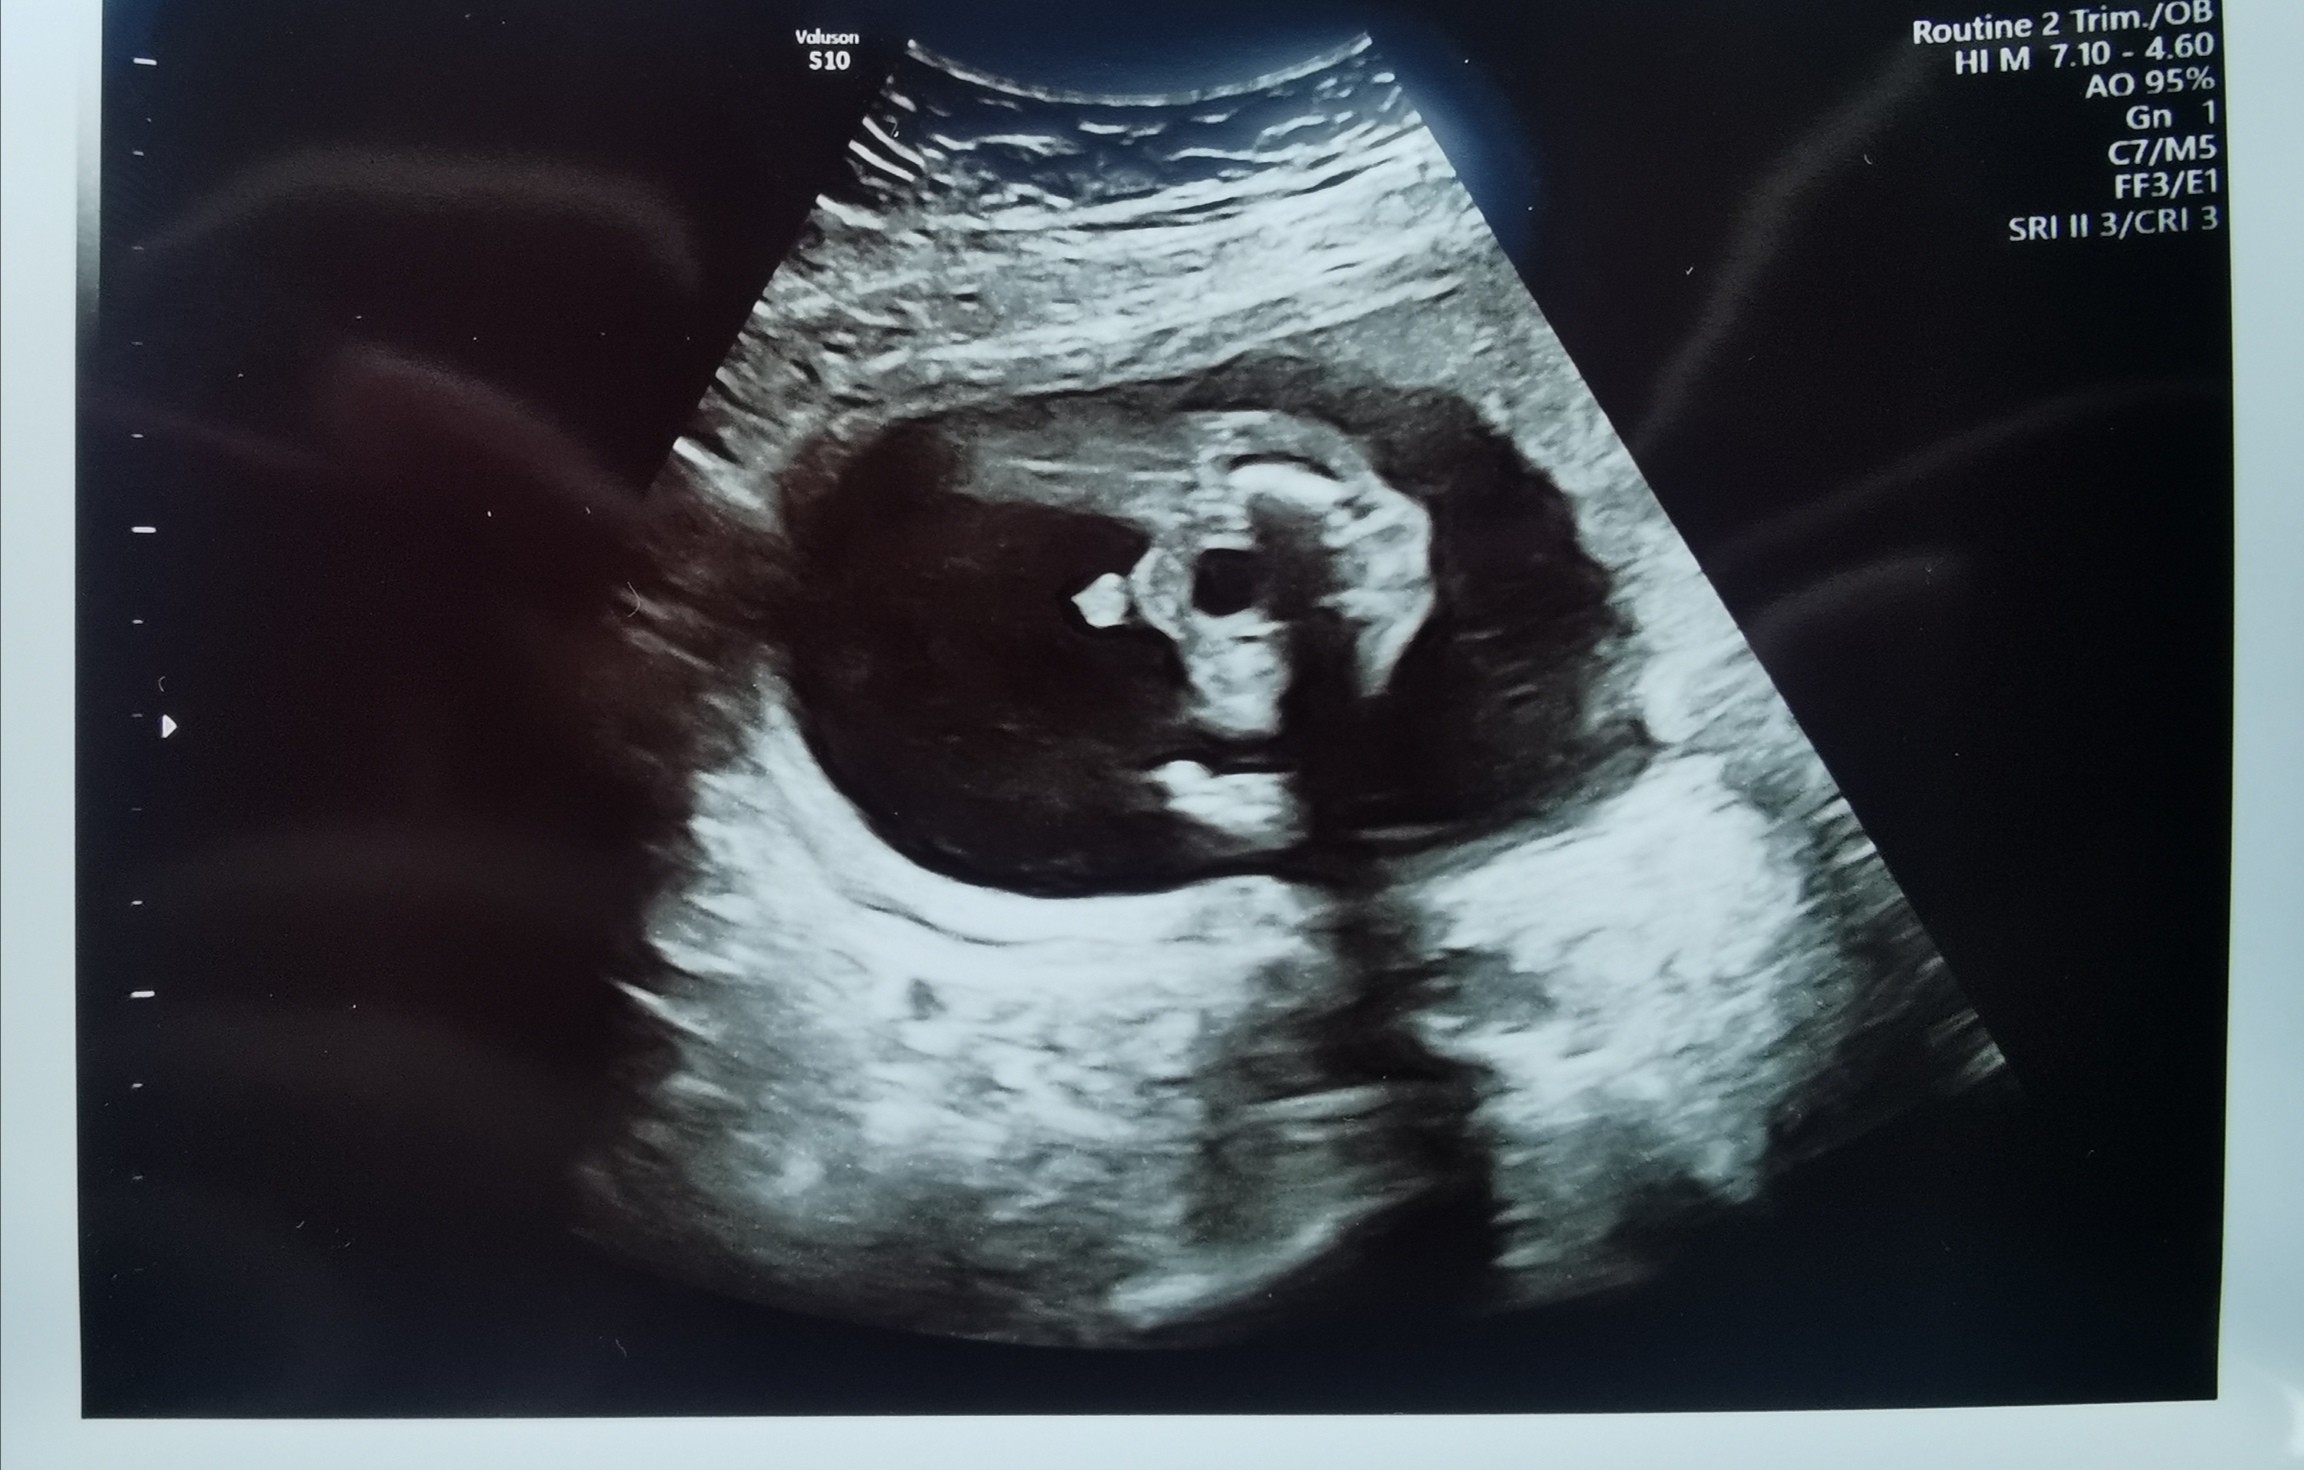

Chłopiec?

Wczoraj mieliśmy podejście do połówkowego - niestety powtórka za 2 tyg bo bobo nie współpracowało w ogóle. Do tej pory nikt nie chciał się wypowiadać odnośnie płci, na pierwszych prenatalnych coś tam dyndalo, ale lekarz powiedział że to za wcześnie i nic nie powie. Teraz p. Doktor (zupełnie inna) od razu nie miała wątpliwości - nie podważam jej umiejętności, ale może to jednak pepowina? 😂 Co myślicie?

Ja mam córkę i na polowkowym inaczej wyglądała między nogami😂😂😂